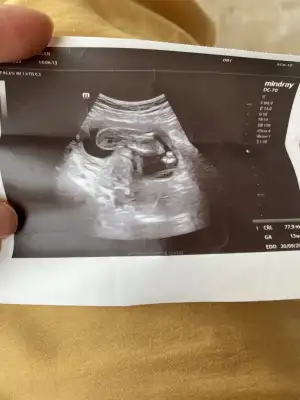

Ben bugün doktora gittim cinsiyeti söylemedi erkek bebek çok istiyorum ama söylemediğine göre kız olabilir yani pozisyon uygun değil gibiydi bu yüzden söylememiş olabilir diye düşünüyorum ya da yanıltıcı olmadın diye üç hafta sonra gel dedi bu da son görüntüsü